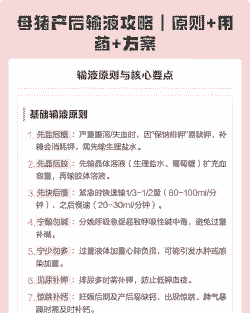

母猪产后输液量应根据具体情况而定,但一般遵循“先快后慢”的原则。具体建议如下:

初期快速输液 :建议用80-100ml/min的速度输完1/3-1/2的输液量,以迅速恢复病理状态、缓解疲劳或抢救死亡。

后期慢速输液:

以20-30ml/min的速度输入其余量。

输液总量:

理论上输液量=已丢失量+每日生理需要量+当日丢失量。但实际应用中常略去生理需要量和当日丢失量,用体重乘脱水程度(已丢失量)除以2,即为实际输液量。

其他注意事项

避免碱中毒:母猪分娩过程中呼吸非常急促,CO2排出太多,容易形成呼吸性碱中毒,因此应遵循“宁酸勿碱”的原则。